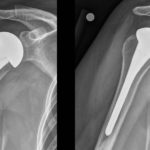

Shoulder Replacement

Courtesy: Dr Thomas Quin Throckmorton, Campbell Clinic Professor, Chief Editor- #AAOS-OrthoInfo REVERSE SHOULDER ARTHROPLASTY Birth of the Modern RSA ” Paul Grammont, Lyon France, 1980’s Constrained shoulder with medialized center of rotation Converts shear forces to compressive forces across glenoid implant – bone interface Outcomes • Average forward elevation 100-134 degrees • Patients do not […]